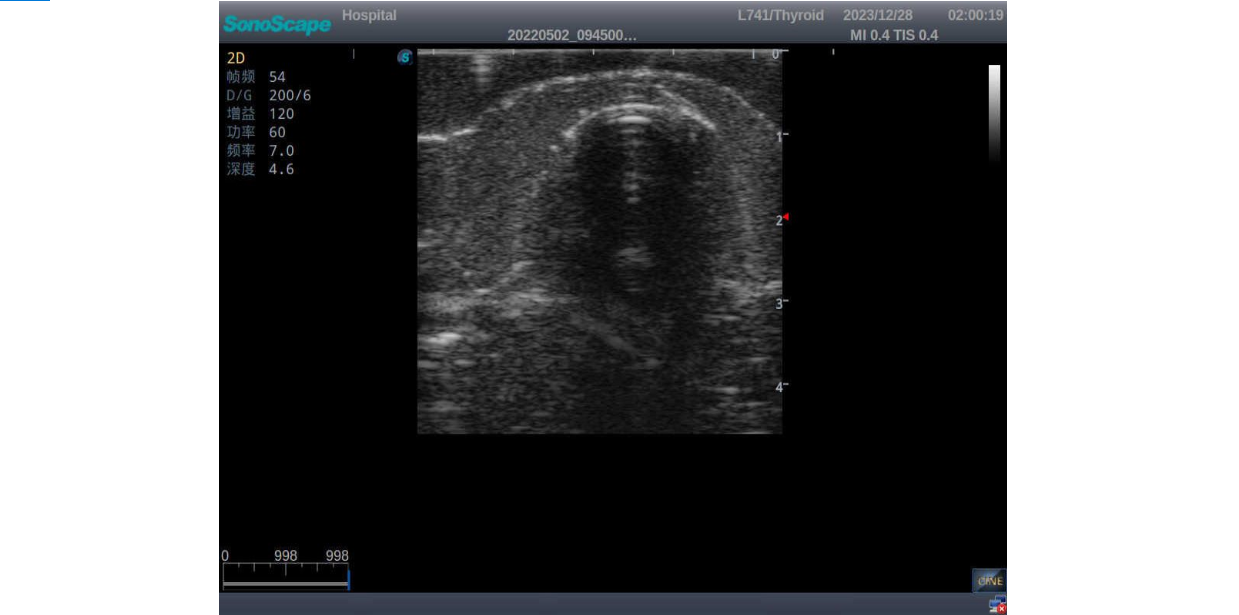

3) It comes with four (4) thyroid modules and can show five (5) ultrasonic images: normal thyroid, thyroid adenoma, thyroid cancer, nodular goiter, thyroid cyst

Thyroid adenoma with well-defined border and smooth uniform halo

Thyroid cancer with irregular mass, unclear border, uneven internal echo or calcification strong echoes